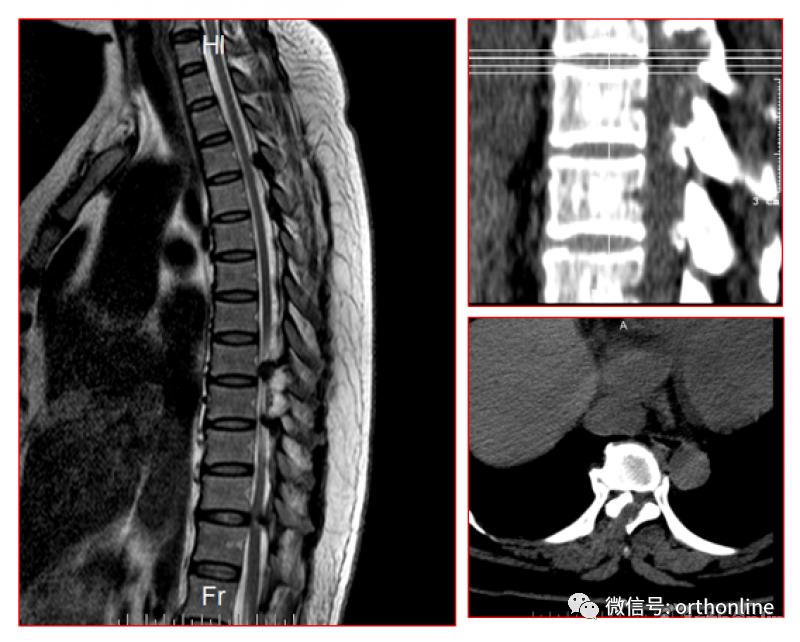

一、黄韧带骨化的分型

1.CT分型:按照轴位CT分为外侧型、延展型、肥厚型、融合型、结节型。

2.MRI分型:按照矢状位MRI分为圆弧形、鸟嘴型。

A.B.圆弧形(Round type);C.D.鸟嘴型(Beak type)

二、后纵韧带骨化形态学分型

1.按照矢状位CT分为线型、鸟嘴型、连续波形、连续圆柱形和混合型。

OPLL的CT矢状位分型为A.线性(Linear type);B.鸟嘴型(Beak type);C.连续波形(Continuous waveform type);D.连续圆柱形(Continuous cylindrical type)。混合型(Mixed type)为同时具有A-D两种及以上类型